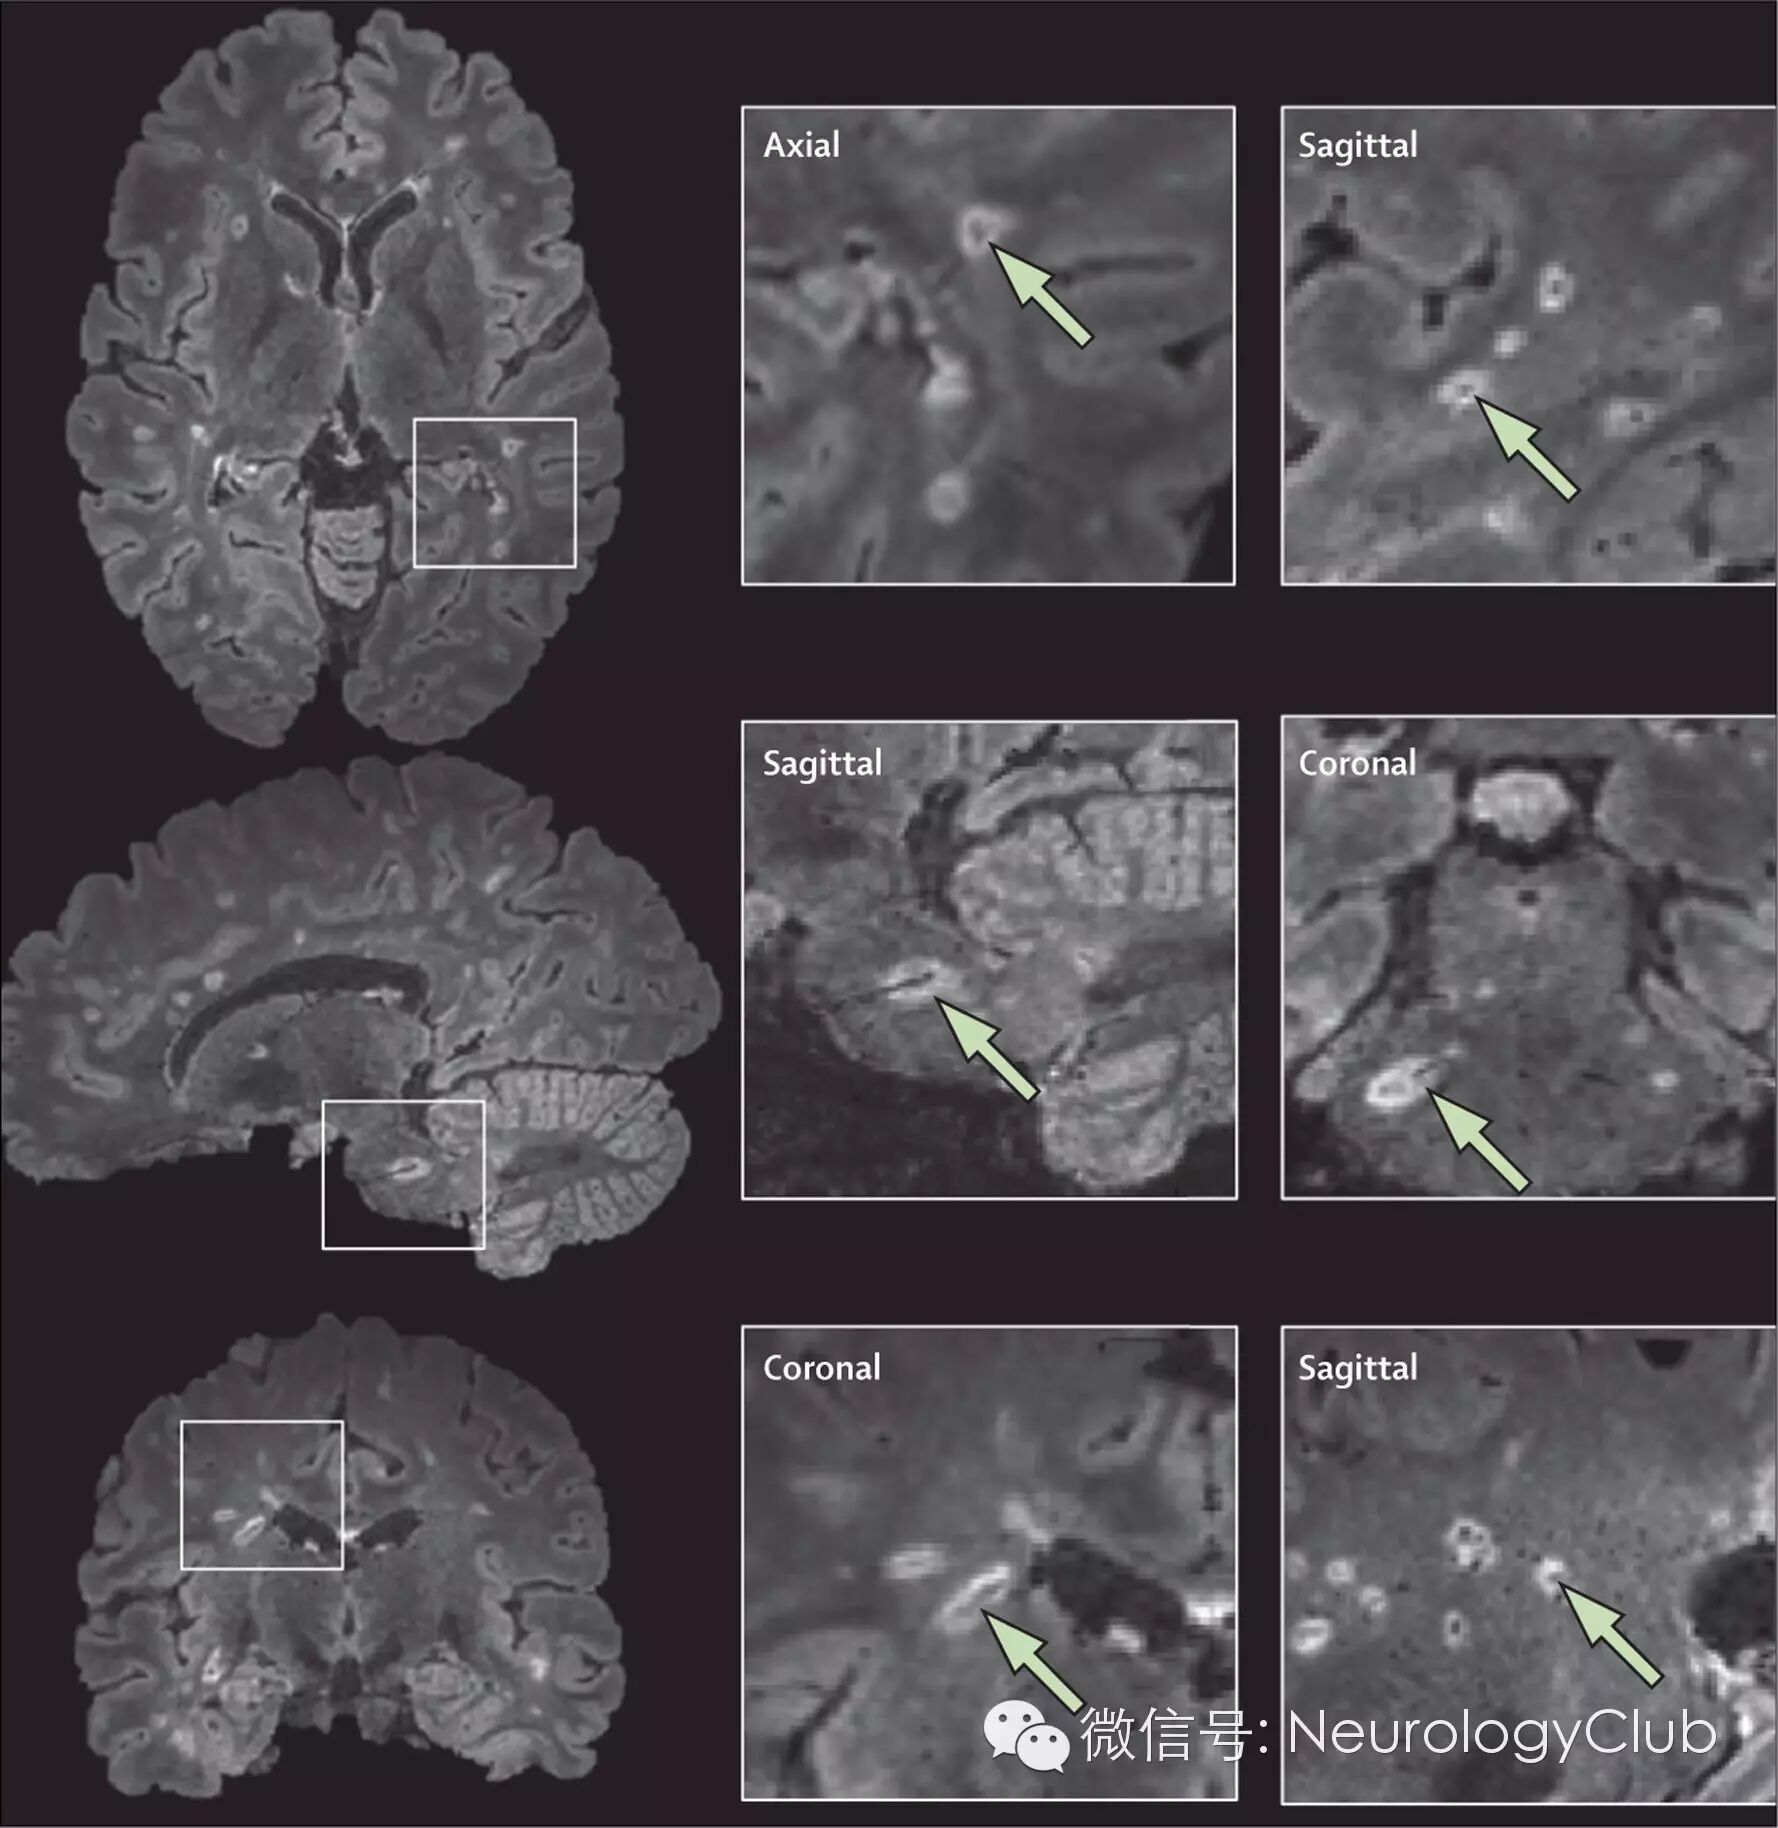

图1  MRI发现的皮质和近皮质病灶

[MRI病灶分类举例基于双反转恢复序列(DIR,左侧列)磁化准备快速梯度回波序列(MPRAGE,中间及右侧列)。第一排:DIR序列上可见1个高信号病灶靠近皮质(绿箭头),但在MPRAGE序列上显示病灶位于白质。第二排:DIR序列上可见1个高信号病灶靠近皮质(绿箭头),MPRAGE序列显示病灶在皮质边缘(近皮质)。第三排:DIR序列上可见1个高信号病灶靠近皮质(绿箭头),MPRAGE序列显示病灶位于皮质内。根据本次修改建议,第二和第三排上病灶均分类为皮质/近皮质病灶]

由于皮质内、灰白质交界和近皮质病灶在传统MRI序列中无法区别,专家共识建议将这些病灶统一为一个术语(皮质/近皮质病灶),包含皮质邻近白质病灶,皮质病灶以及同时累及两者的病灶,以此扩大2010年McDonald标准DIS中近皮质病灶的范围。如可能,建议使用先进的影像设备发现皮质病灶。